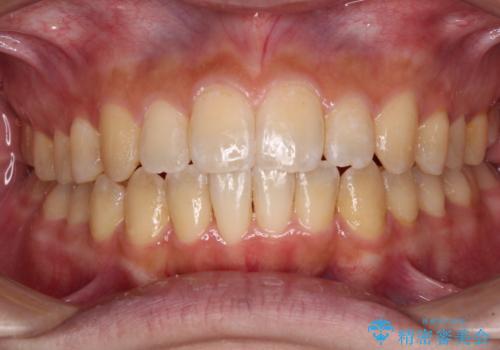

[ 前歯開咬 ] 前歯が噛んでいない マウスピース矯正治療

![[ 前歯開咬 ] 前歯が噛んでいない マウスピース矯正治療の症例 治療前](https://seimitsushinbi.jp/wp/wp-content/uploads/2022/11/IMG_4669-500x350.jpg?v=1668218426)